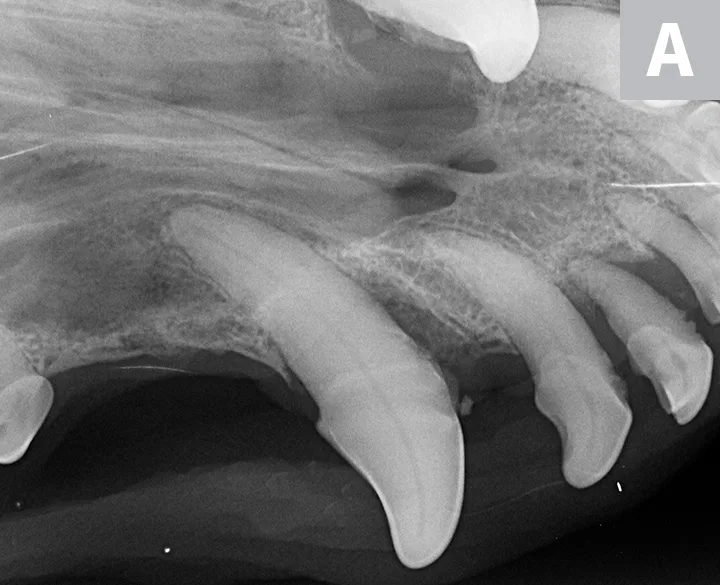

Figure 2

Dental radiographs of the right (A) and left (B) maxillary canine teeth (lateral views) and the rostral maxillae (C; occlusal view) confirmed mild horizontal and severe vertical bone loss at the mesial aspect of both maxillary canine teeth. Moderate to severe horizontal bone loss at the right maxillary first incisor tooth (blue arrow) and total loss of attachment with inflammatory root resorption at the right maxillary second incisor tooth (yellow arrow) were present. The remaining maxillary incisor teeth were affected by mild horizontal bone loss. Although the occlusal view of the rostral maxillae is slightly asymmetric, osteolysis was evident in the area of the left palatine fissure (red arrow). Mild horizontal bone loss was diagnosed at several other teeth. In addition, retained root tip of the left maxillary (presumably) first premolar tooth (white arrow) was identified.